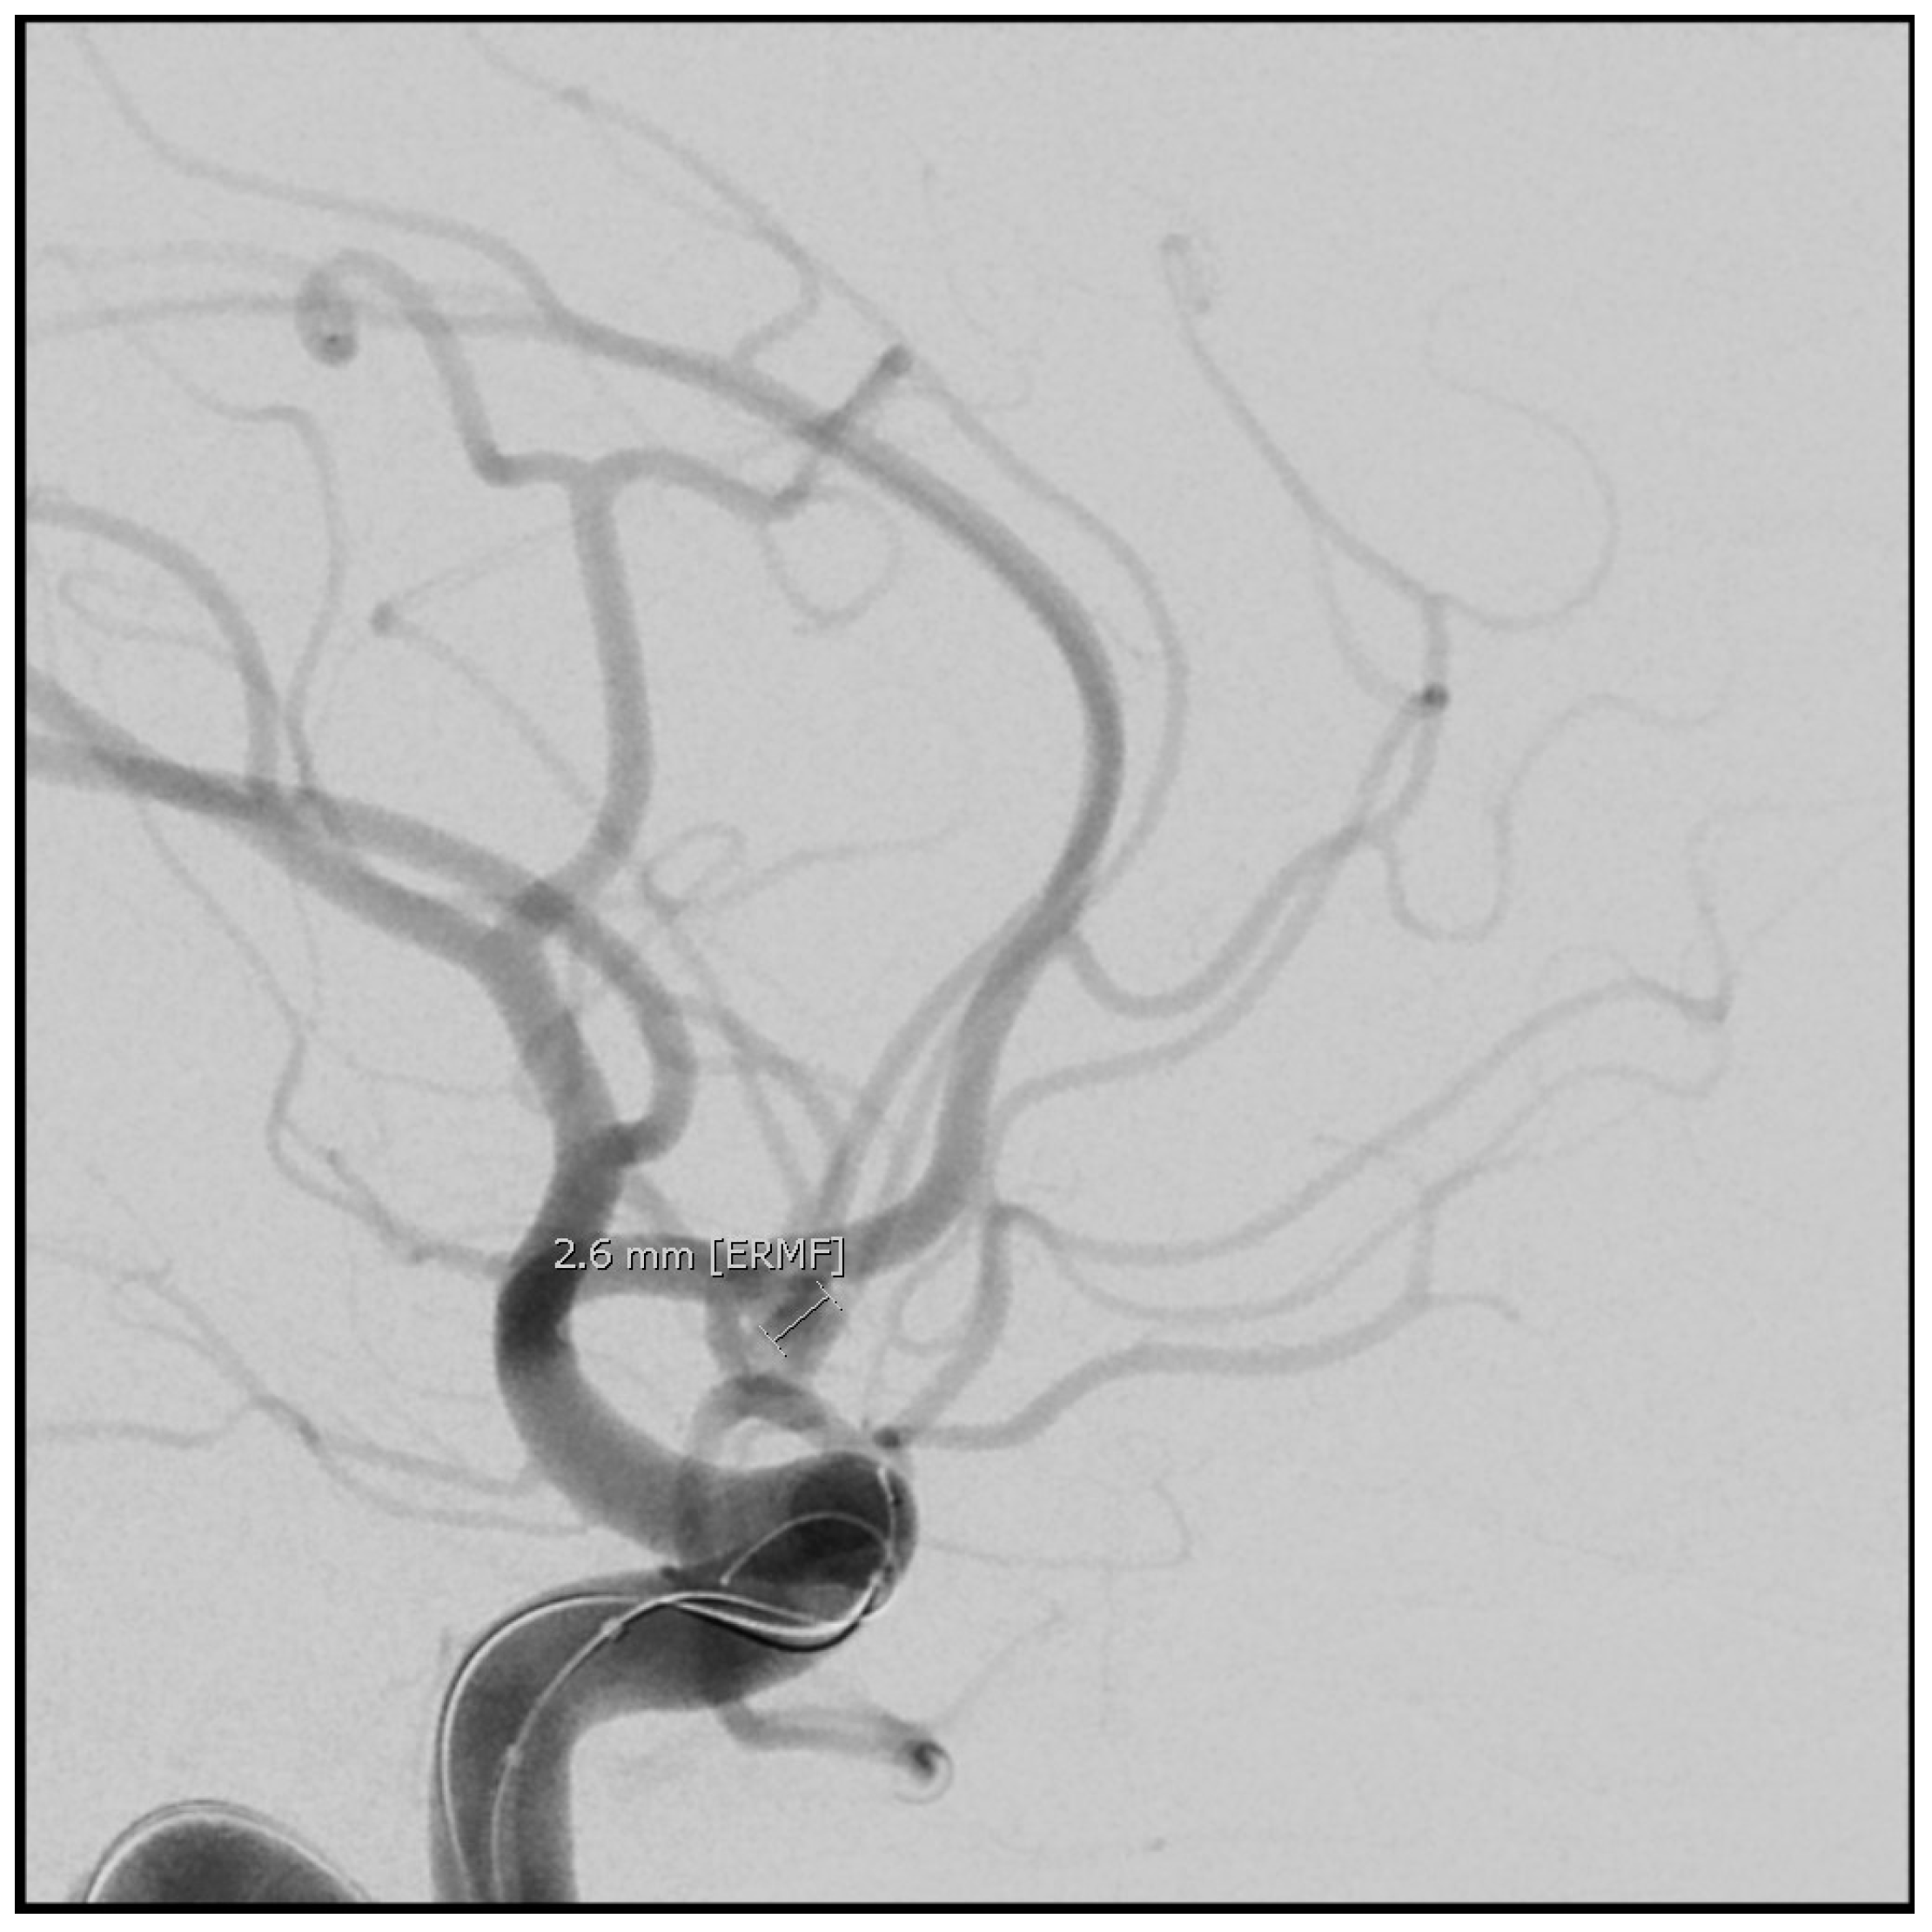

7. Aneurysm Repair